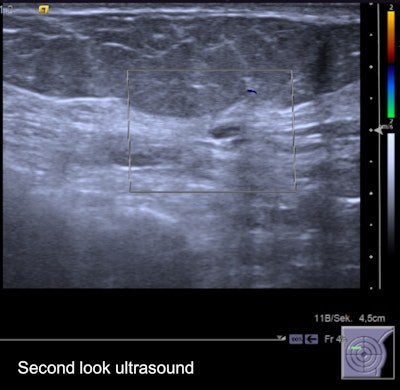

Second-look ultrasound of the lesion. It's an oval, horizontally oriented lesion with circumscribed borders, posterior acoustic enhancement, and no hypervascularization. Internal features unspecific hypoisoechoic. It was found to be probably benign on ultrasound, and followed up over two years without evidence of growth.

Second-look ultrasound of the lesion. It's an oval, horizontally oriented lesion with circumscribed borders, posterior acoustic enhancement, and no hypervascularization. Internal features unspecific hypoisoechoic. It was found to be probably benign on ultrasound, and followed up over two years without evidence of growth."We all do a lot of examinations; most of them we do not immediately get feedback from," he said. "I heard doctors from the German screening program brag, calling their sensitivity 100% -- that is of course they see the cancers they detect, not the ones they miss. Regarding second-look ultrasound, it is similar and a lot of things can be taught: How often do I find a correlate for MRI lesions? Can I also see nonmass lesions? Can I upgrade or downgrade lesions using ultrasound? What lesions am I likely to miss and can I do anything about it?"